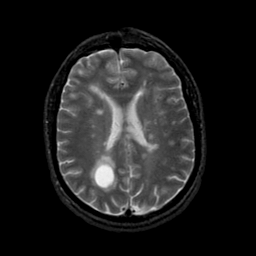

MR Study #21, November 3, 1991 -- Slice #31